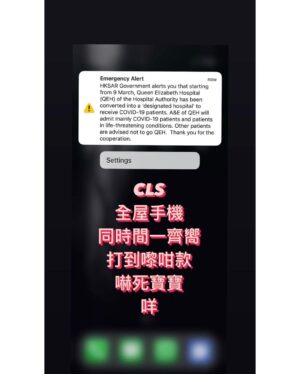

1.8K Likes – Bonnie Chiu Hok-Yee Instagram

Caption : 曲你個乖 嚇到個心離晒罩喎 我倆老以為自己有幻覺 :咩聲呀 :係咪地震警報? :我哋中咗感冒? 虎你咩!Likes : 1750